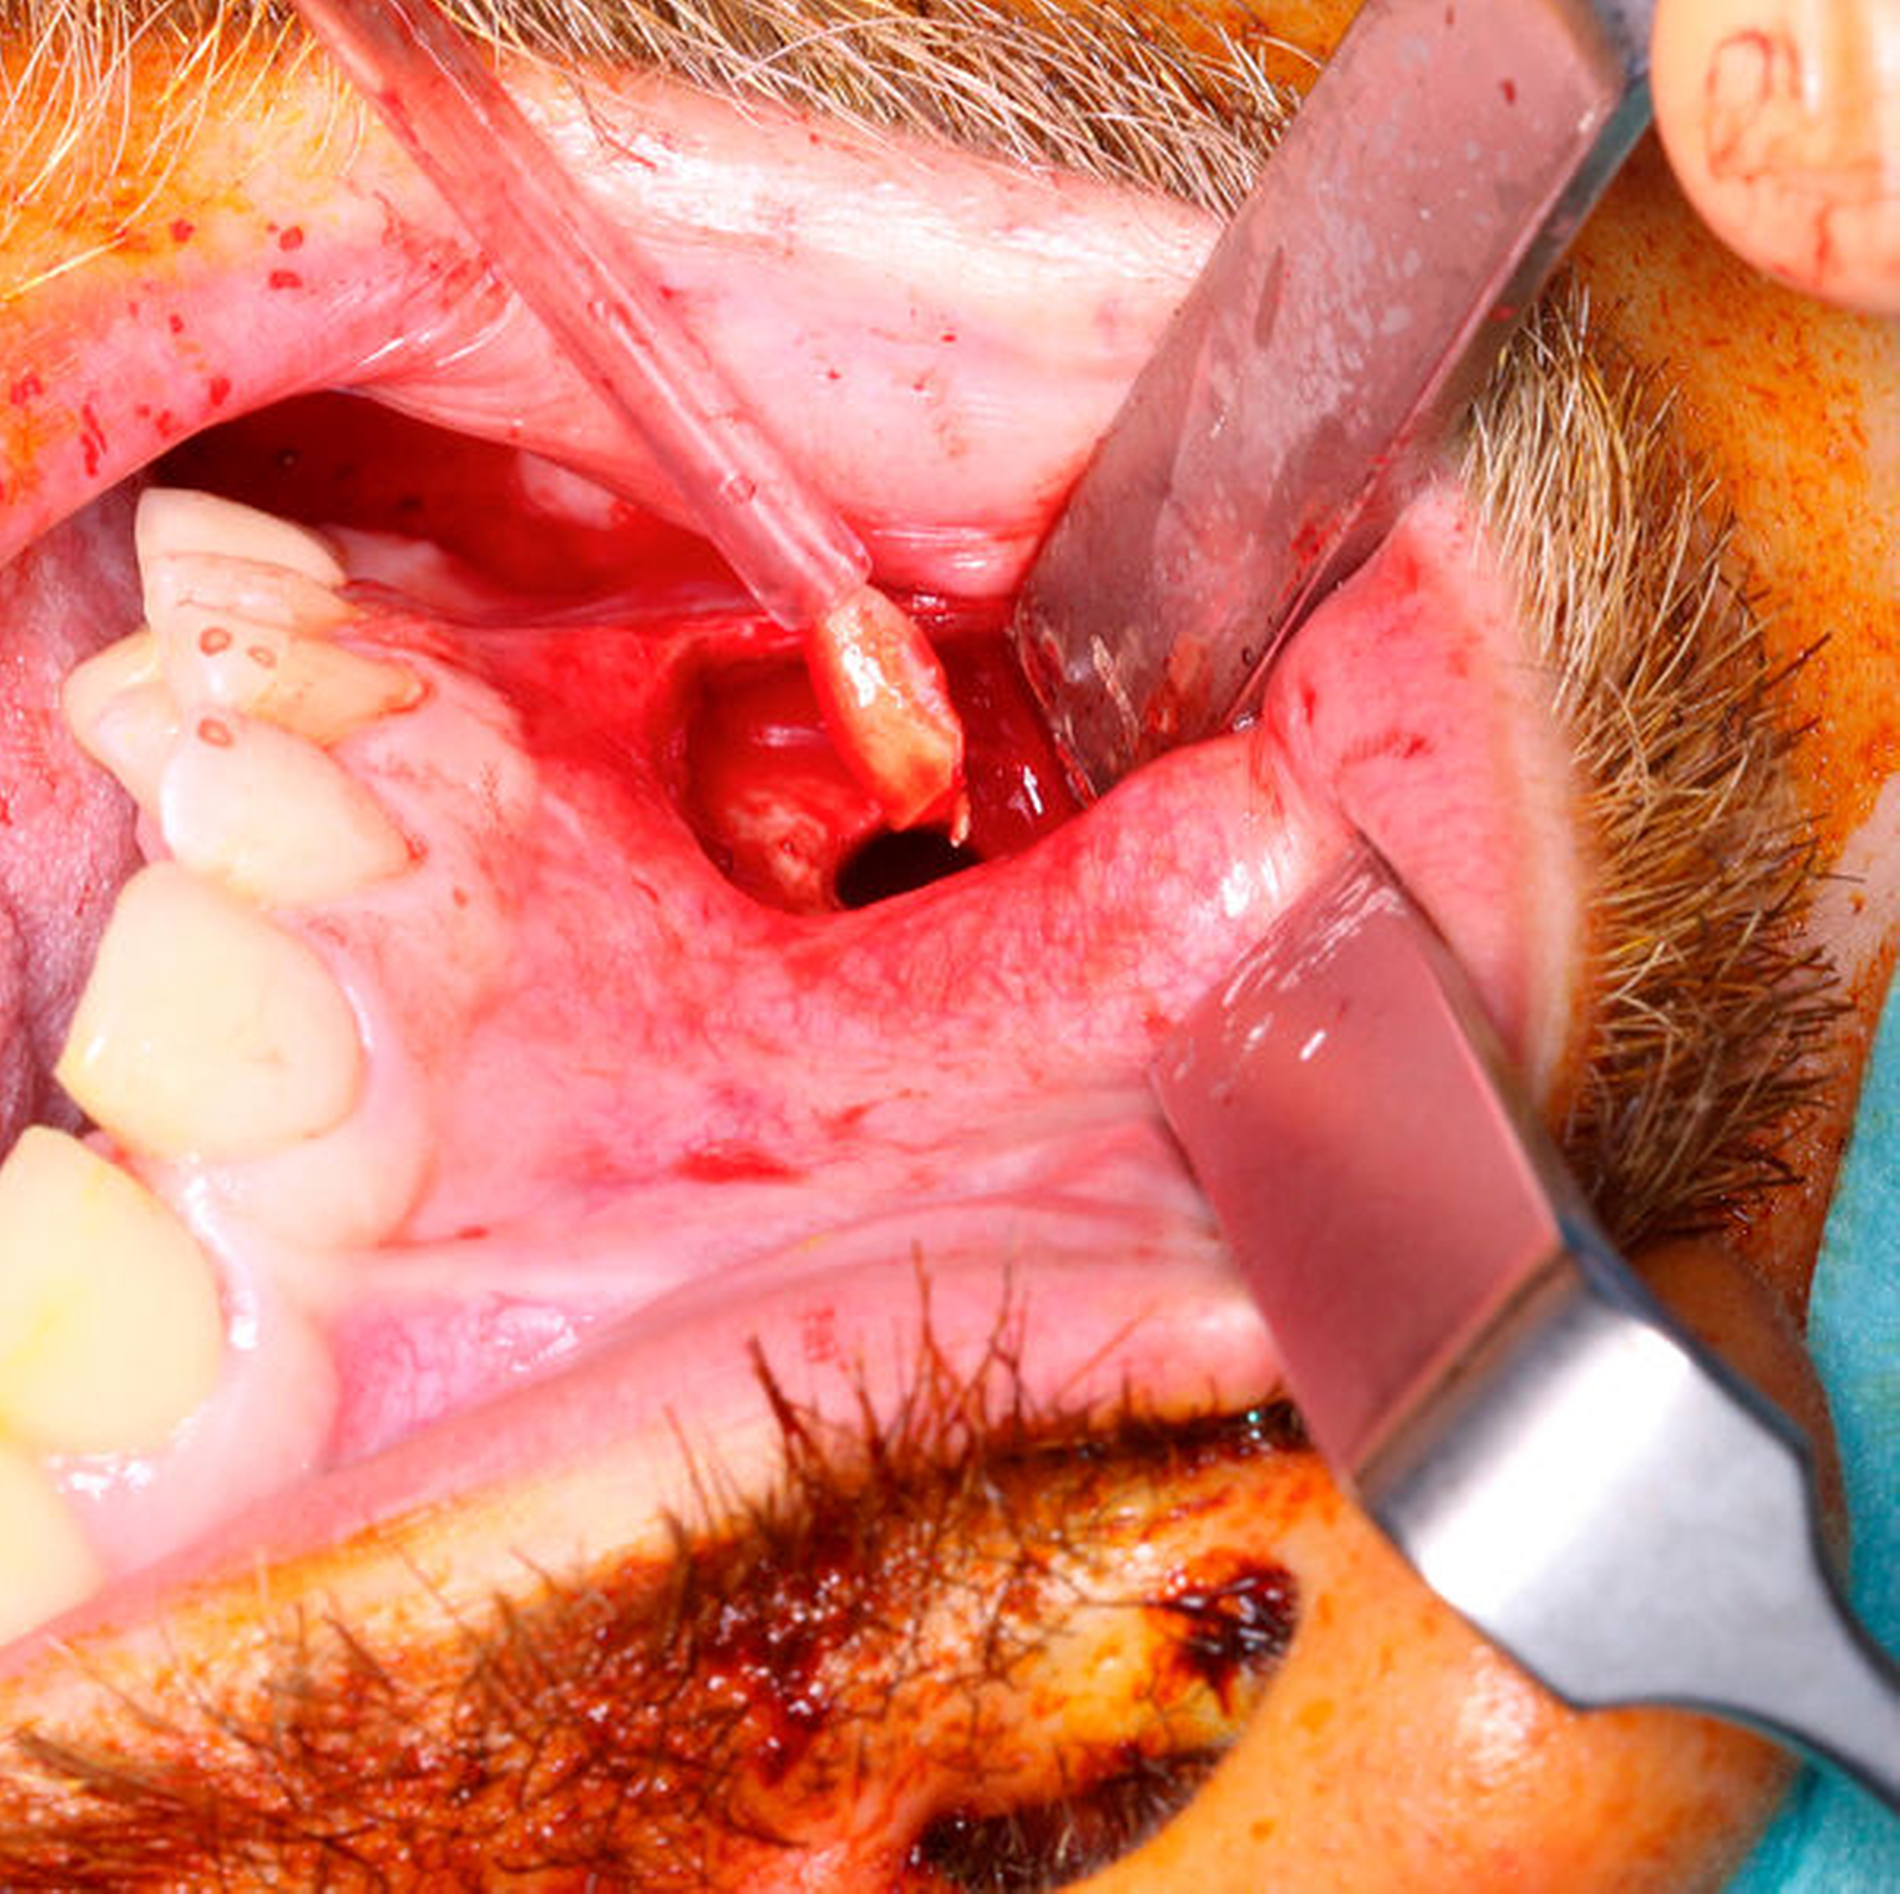

Wir klärten beide Patienten ausführlich über das vorliegende Krankheitsbild auf und entschieden uns in beiden Fällen für eine endoskopische Operation. Anders als beim osteoplastischen Zugang mit Anlegen eines relativ großen Knochendeckels und somit vergleichbar großen Knochendefekts in der Kieferhöhlenwand, wird bei der Endoskopie lediglich ein circa 7 mm x 7 mm bis 9 mm x 9 mm großes, rundes Knochenfenster benötigt (Abbildung 3), das mit dem Bohrer angelegt wird. Der Eingriff beginnt mit der Infiltration von 1,5 ml Articain (mit Adrenalinzusatz 1:200.000). Über einen circa 1,5 cm langen Schnitt kranial der mukogingivalen Grenzlinie im Bereich des Eckzahns wird hierbei der Knochen im Bereich der Fossa canina freigelegt. Die Bohrung wird circa 5 mm kranial der Prämolaren durchgeführt. Über diesen Zugang kann nun die Kamera mit 0°- oder 30°-Optik eingeführt und in der Regel die gesamte Kieferhöhle eingesehen werden.

Bei Patient Nr. 2 war die verbliebene Wurzelspitze nach Einbringen der Kamera ebenfalls sofort identifizierbar (Abbildung 7). Durch die präoperative CT-Diagnostik waren Lage und Größe des Wurzelrests eruierbar, so dass mithilfe des Saugers der Fremdkörper problemlos durch den angelegten Zugang entfernt werden konnte (Abbildungen 8 und 9). Es zeigte sich ein deutlich entzündlich veränderter Sinus, der nach der Entfernung mehrmals mit steriler Kochsalzlösung gespült wurde.